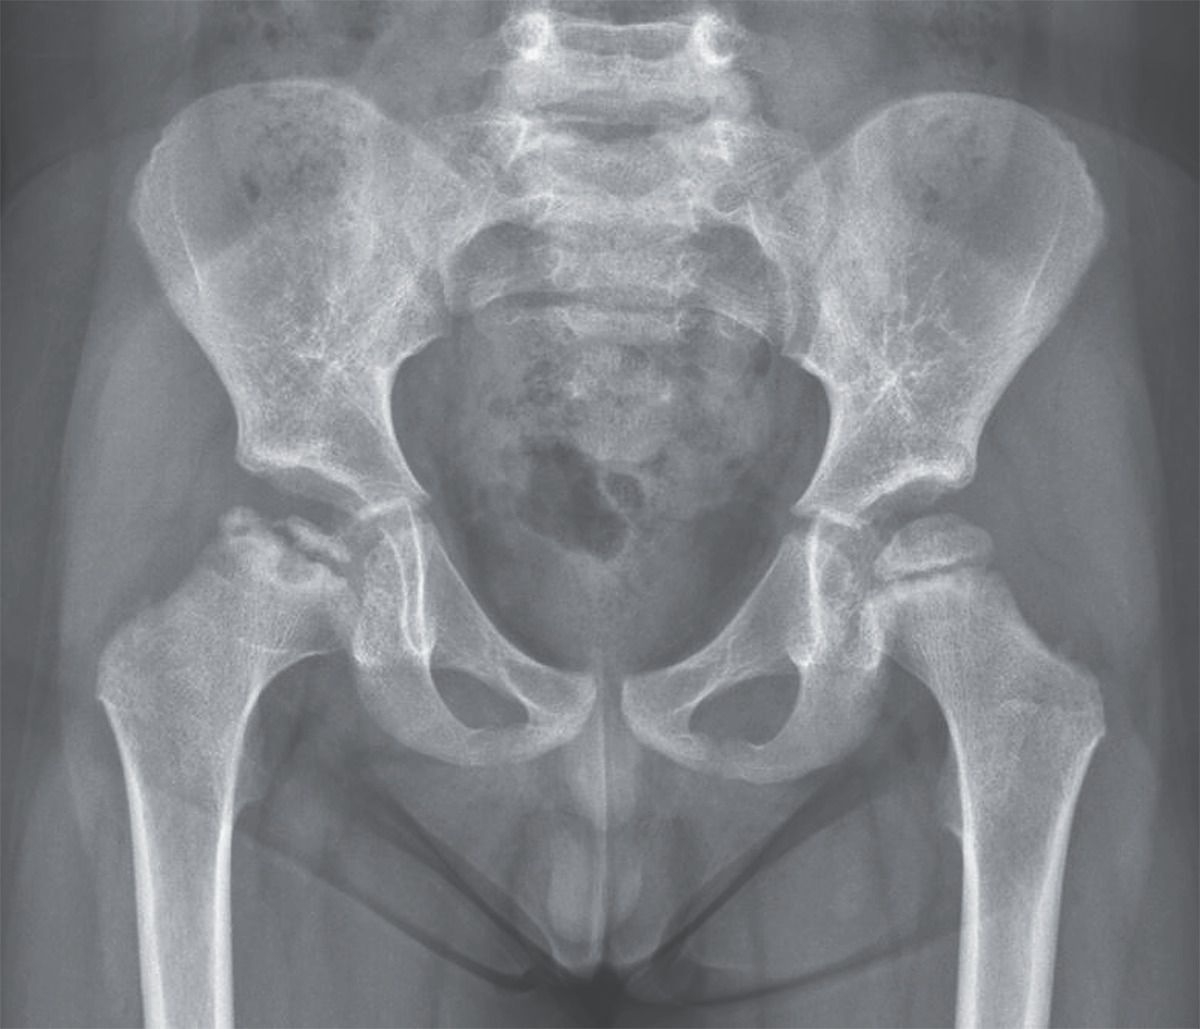

A 4-year-old boy was brought to the orthopedic clinic with a 2-day history of pain in the right hip and limping. There had been no preceding trauma or fever. Physical examination showed no limitation in hip range of motion on either side. There was an antalgic gait favoring the right side but no discrepancy in leg length and no soft-tissue changes or neurologic abnormalities. A radiograph of the pelvis showed a focal area of collapse in the right femoral head. A diagnosis of Legg–Calvé–Perthes disease was made. Legg–Calvé–Perthes disease is an idiopathic avascular necrosis of the femoral head in preadolescent children. It manifests as acute- or insidious-onset hip pain or limping, and the differential diagnosis includes infection, trauma, and synovitis. Early in the course of the disease, plain radiographs may appear normal. Treatment with short-term bracing was initiated to maintain hip abduction within a range of approximately 30 degrees to contain the femoral head within the acetabulum. The patient was also advised to avoid high-impact physical activity and was reassured with regard to an expected favorable prognosis. At the 2-month follow-up visit, the patient’s pain and limping had resolved.